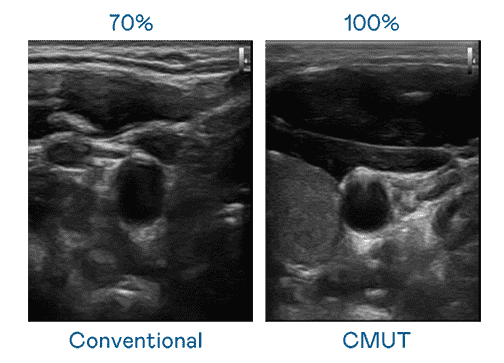

CMUT 技术是一种用电容式微机电元件来产生超音波讯号的技术。。与传统 PZT 压电式技术相比,,CMUT 频宽增加 30%,,,更宽频的超音波讯号让影像解析度大幅提升,,,是实现高影像品质医疗超音波扫描、、、促进精准医疗发展的关键技术。。。。

超音波影像的解析度高低,,,首先取决于探头能发出的讯号频宽。。。蓝狮在线 CMUT 可提供高清晰的超音波讯号,,,,提供高频宽、、、高灵敏度、、影像纹理细节更高的超音波影像,,协助医护人员缩短影像判读时间及利用精准的医疗影像进行诊断。。